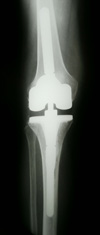

During knee replacement surgery, an orthopaedic surgeon will resurface your damaged knee with artificial components, called implants.

In total knee replacement, damaged bone and cartilage are removed and replaced with metal components that recreate the surface of the joint.

Implant Components